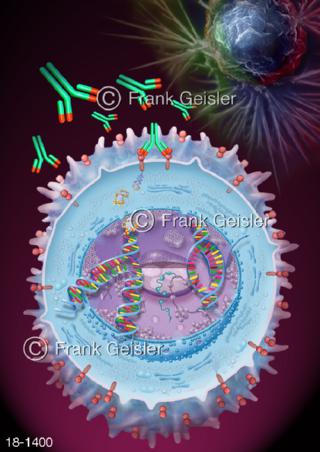

18-1400 Brustkrebstherapie mit Herceptin Trastutumab